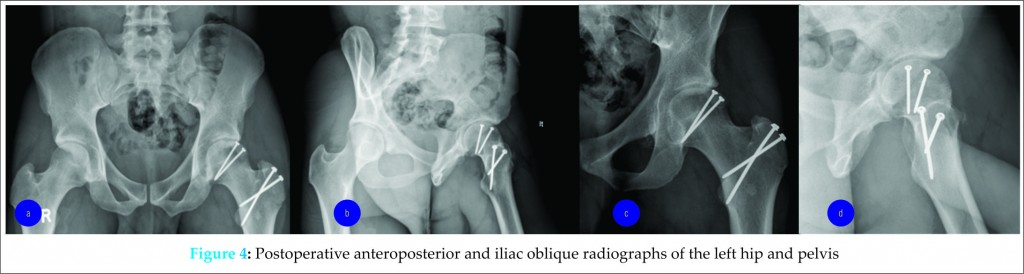

The patient returned for follow-up at the eighth postoperative week, having missed his previously scheduled appointments. Despite strict instructions regarding weight bearing, he was ambulating with full weight on the operative extremity, without assistive devices and complaining of minimal pain. The patient endorsed non-compliance with activity restrictions, beginning approximately two weeks after surgery, secondary to a decrease in pain, improved range of motion and his being unable to take additional time off work. Physical exam of the left hip revealed a well-healed incision without clinical signs of post-operative infection. Examination of hip range of motion demonstrated flexion of 0-110°, internal rotation of 15°, external rotation of 20° and abduction of 15°. Radiographs demonstrated maintenance of alignment and congruity of the left hip joint with stable internal fixation of both the graft and trochanteric osteotomy. As the patient had been performing well despite non-compliance with restrictions, his activity was advanced to weight-bearing as tolerated.

At six months post-operatively, the time of last follow-up, the patient endorsed minimal pain, no limitations with regard to his activities of daily living or his ability to perform the duties of his occupation as a manual laborer. The pain was localized primarily to the greater trochanter, which subsequently improved after a local injection of 40mg of triamcinolone acetonide. A Harris Hip Score of 83 was calculated (good = 80-90). Range of motion about the left hip demonstrated 0-120° of flexion/extension, internal rotation of 40°, external rotation of 40°, abduction of 40° and adduction of 30°. Radiographs demonstrated a concentric hip joint with interval healing without evidence of collapse, implant loosening, implant failure or secondary arthritis (Fig 4).